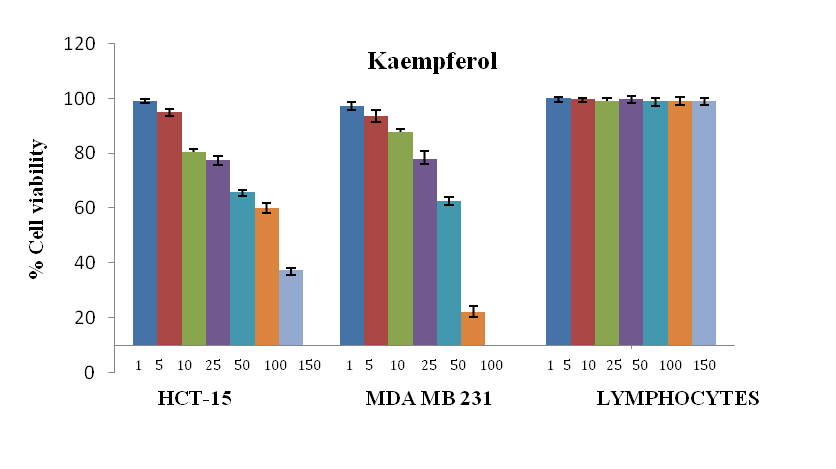

Effect of kaempferol on cell growth

The growth of cancer cells was inhibited in a dose-dependent manner after exposure to the phytochemical (fig. 1, 2), whereas normal human lymphocytes were not affected after exposure (fig. 3). The effect of flavonoid kaempferol on the proliferation of two cancer cell lines (HCT-15 and MDA MB 231) and normal lymphocytes were determined using MTT assay. The IC50 values for kaempferol on HCT-15 and MDA MB 231 were evaluated as 120±3.2 µg/ml and 64±1.2 µg/ml respectively (table 1). When the activity of kaempferol against cancer cells was compared with that against normal lymphocytes it was evident that kaempferol had specific anti-proliferative activity against the two cancer cell lines tested (fig. 4). Further studies were performed based on the IC50 concentrations.

Kaempferol, a flavonoid antioxidant, is an active constituent in many of the fruits and vegetables. It is one of the most commonly consumed dietary supplements [8, 18]. In recent studies, many reports demonstrated preventive and therapeutic efficacy of kaempferol in several epithelial cancer models [17, 19]. Recent epidemiological studies show that many cancer patients use alternative medicine, mostly of herbal origin. The present study shows that kaempferol is one such agent, which is nontoxic, consumed widely as a dietary supplement, and possesses strong anticancer activity against different epithelial cancers.

Fig. 4: Anti-proliferative activity of kaempferol on human colon cancer cells (HCT-15), breast cancer cells (MDA-MB 231) and lymphocytes